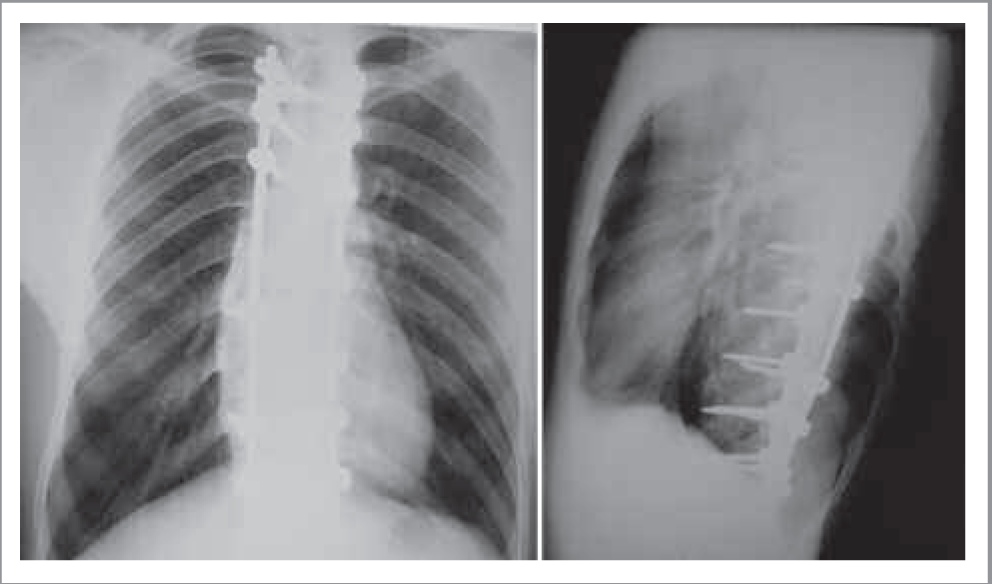

Кроме того, с учетом наличия в анамнезе у пациента указаний на проведенные оперативные вмешательства нам предоставлены рентгенологические снимки и данные компьютерной томографии (КТ). На рентгенограммах грудной клетки в прямой и левой боковой проекциях визуализируются результаты металлоостеосинтеза сколиотической деформации грудной клетки, транспедикулярная конструкция для фиксации грудопоясничного отдела позвоночника (рис. 2). Такие изменения скелета, возможно, связаны с выявленными дефектами, но могут иметь и самостоятельное значение в виде сопутствующего заболевания пациента Г. – синдрома недифференцированной дисплазии соединительной ткани. У пациента данный синдром характеризуется следующими фенотипическими признаками: торакодиафрагмальным синдромом, включающим в себя деформацию позвоночника (выраженный сколиоз, потребовавший хирургического лечения), синдромом гипермобильности суставов, клапанным синдромом, проявляющимся пролапсом митрального клапана [12].

Рис. 2. Рентгенограммы пациента Г. Транспедикулярная винтовая система для фиксации грудопоясничного отдела позвоночника.